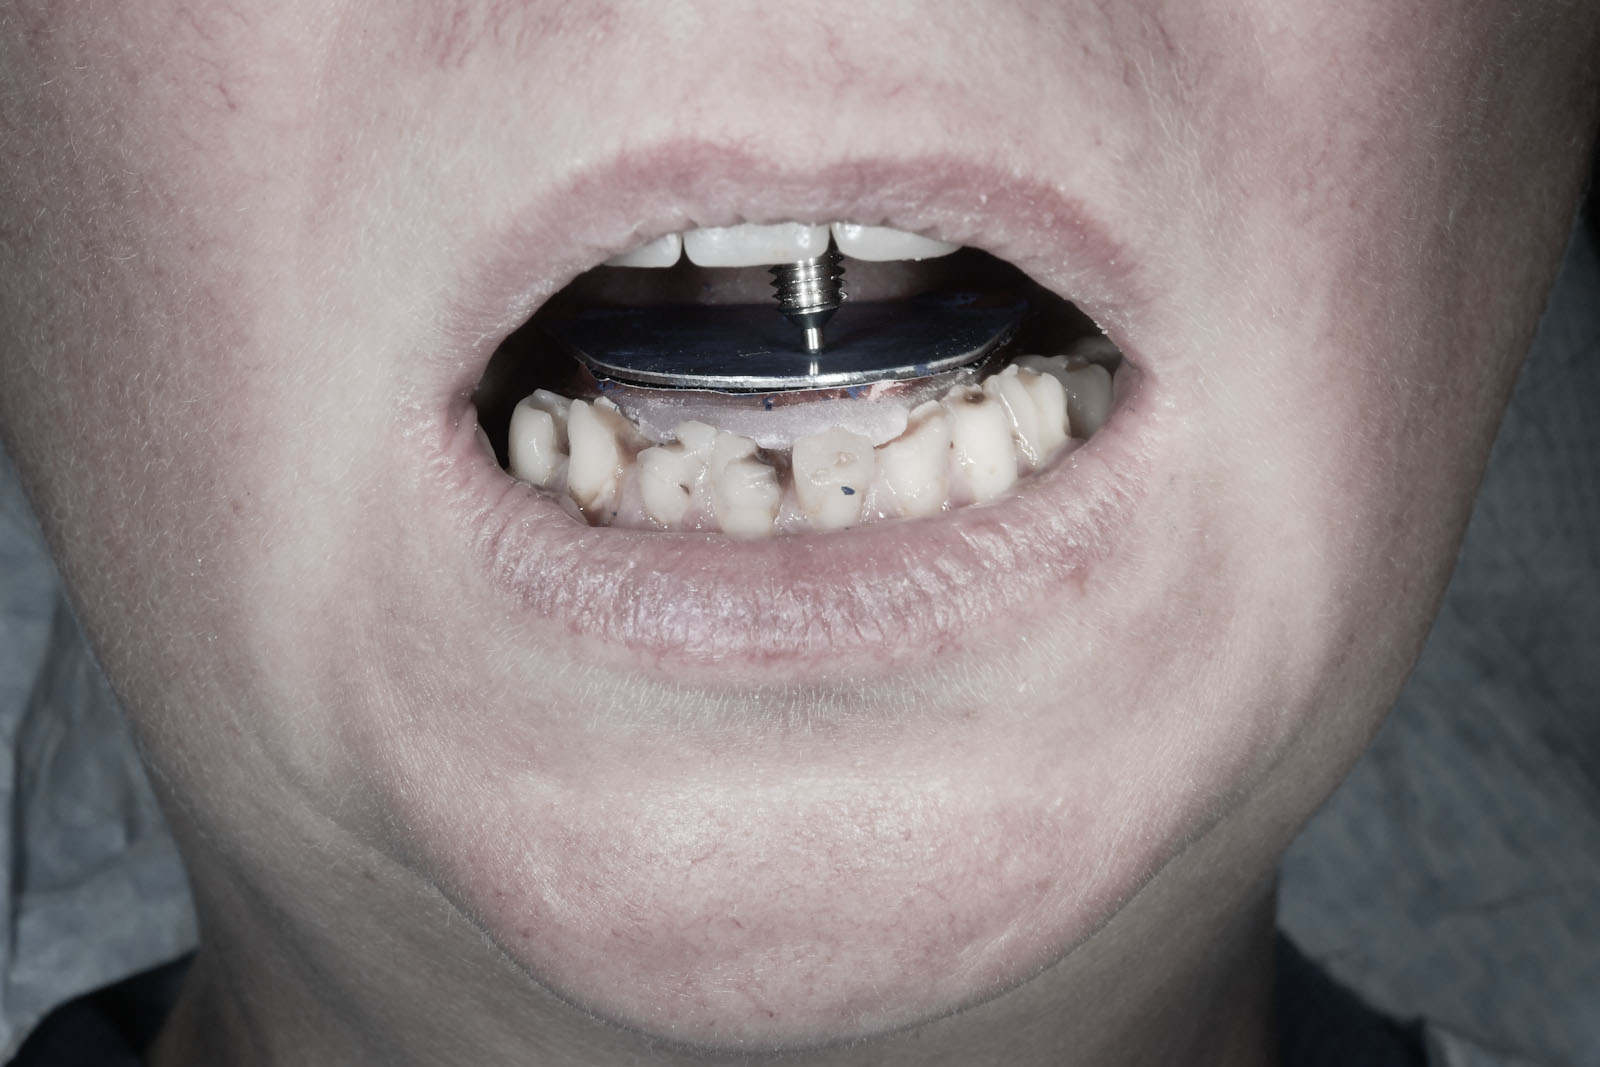

W celu ustalenia wzajemnej relacji żuchwy i szczęki Gerber poleca rejestrację z użyciem centralnego sztyftu podpierającego, który zapewnia równomierne obciążenie podłoża protetycznego i stawów skroniowo-żuchwowych, a także ułatwia centralne ułożenie głów stawowych dzięki trójpunktowemu podparciu żuchwy w stosunku do czaszki.

W pierwszym etapie wykonuje się modele robocze, które są montowane w opracowanym przez prof. Gerbera artykulatorze. Tak zwany condylator pozwala na symulację trójwymiarowych ruchów głów żuchwy. Pozwala na zweryfikowanie poprawności relacji pomiędzy łukiem zębowym górnym a dolnym. Po dokładnym zbadaniu funkcji i morfologii stawu sż, wykonaniu pomiarów oraz ocenie stanu zdrowia zębów zostaje opracowany indywidualny plan leczenia zgodny z uwarunkowaniami pacjenta.

Dzięki zastosowaniu łuku twarzowego możliwy jest pomiar kątów nachylenia torów przesuwania głów żuchwy. Pozwala to na zamontowanie modeli gipsowych w stosunku do stawów skroniowo-żuchwowych i płaszczyzny Campera (linii uszno-nosowej) orientacyjnej w widoku z profilu. Ma to na celu odtworzenie prawidłowej okluzji, czyli odpowiedniej pozycji stykania się zębów górnych z dolnymi.